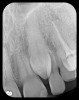

There are two specific types of DIDR sensor systems available to dentists in the marketplace: the hard-wired (HW) sensor and the photostimulable phosphor (PSP) sensor,1,2 also commonly known as phosphor "plates." A desirable feature common to both modalities is the ability to expose either bitewing (BW) or PA radiographic images. The BW radiograph (Figure 1) is usually considered more appropriate for caries detection, whereas the PA (Figure 2) is diagnostic for several different anatomic and pathologic issues.7

Fig 2. Left: PSP vertical PA radiograph of

maxillary bicuspid area demonstrating full root structure, several millimeters of bony anatomy beyond apices and maxillary sinus. Tooth No. 4 may be

traumatized as periodontal ligament is widened. Right: PSP horizontal PA radiograph of maxillary bicuspid area. Tooth No. 12 shows widened apical

periodontal ligament presumably caused by deep restorative filling. Some loss of supporting bone is evident interproximally, especially pronounced

between tooth Nos. 14 and 15.

Figure 2